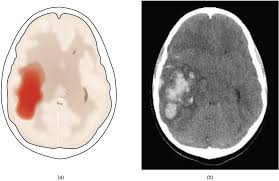

뇌경색이란

무엇인가 뇌경색은 뇌혈관이 혈전이나 지방 침착 등으로 막혀 뇌에 혈액 공급이 중단되는 상태를 말합니다.

뇌세포는 산소 공급이 끊기면 몇 분 내에 손상되기 시작하므로, 신속한 치료가 필수적입니다.

이 질환은 고혈압, 당뇨, 고지혈증 등 만성질환과 밀접하게 연관되어 있습니다.